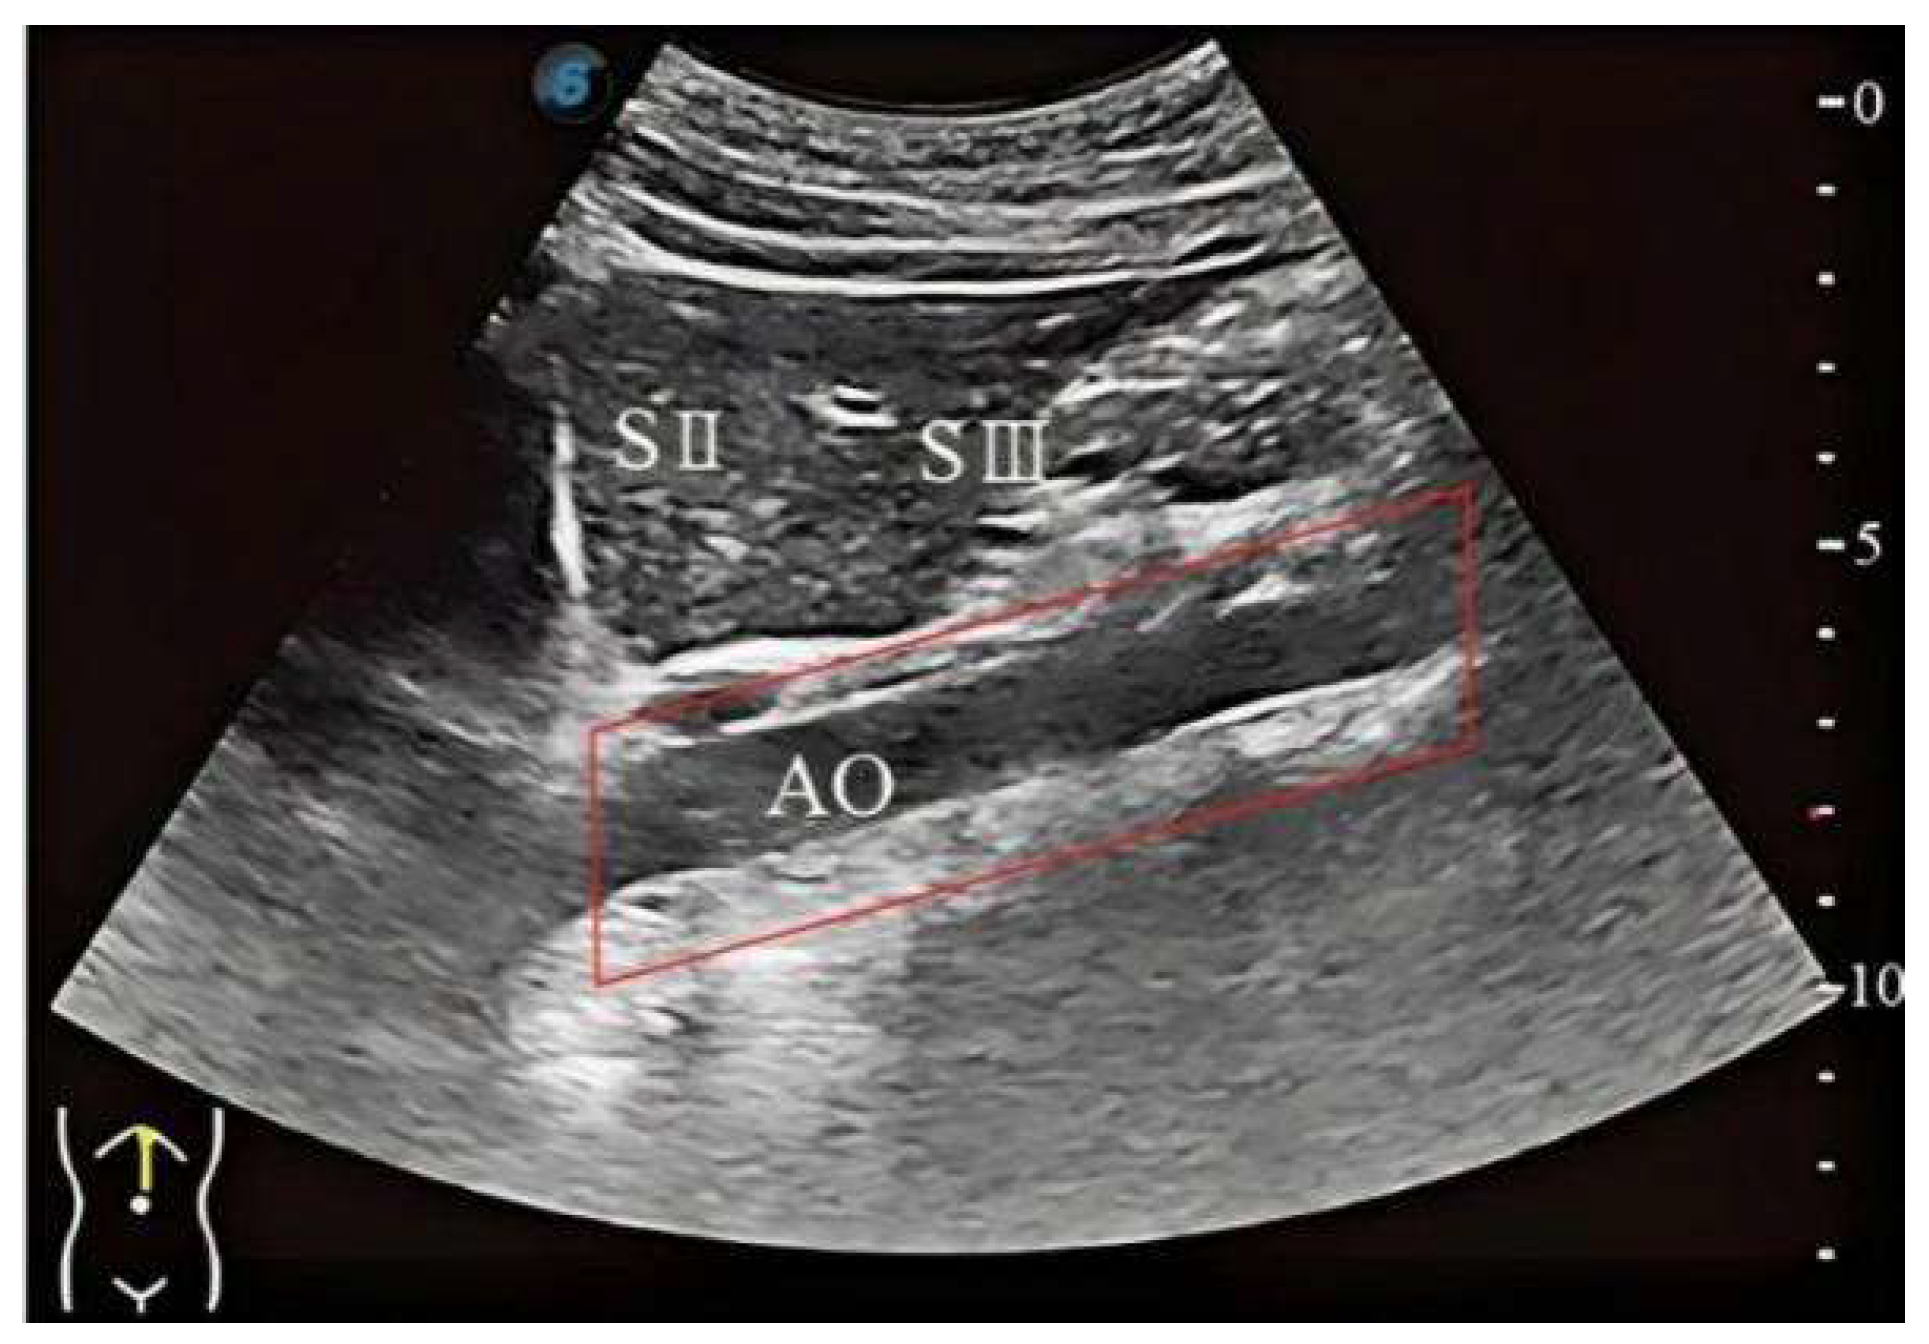

3.2. Liver Standard Plane Localization

4.2. Image Segmentation and Recognition Results

4.3. Experiment Results of the Reinforcement Learning Agent